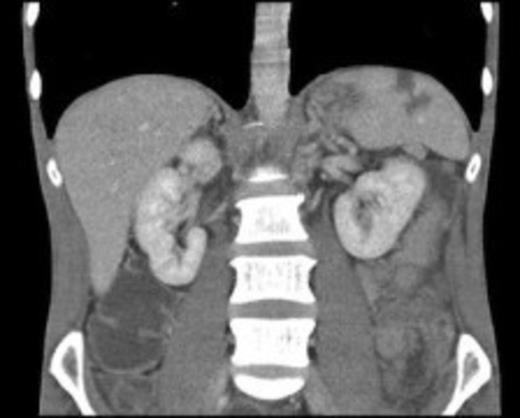

CT showing evidence of splenic infarction secondary to infective endocarditis

A provisional diagnosis of alcohol-induced pancreatitis was made. He received standard management as mild pancreatitis (Glasgow score 0) with ward level care. An ultrasound showed no abnormality. Due to diagnostic uncertainty and failure of symptoms and signs to rapidly resolve, a CT abdomen was performed. This demonstrated a normal looking pancreas but evidence of splenic infarction (Figure). Subsequent echocardiogram for a source of emboli showed multiple valvular vegetations, aortic regurgitation and a 16mm pericardial effusion. Blood cultures yielded Group-A streptococcus. Poor dentition was deemed to be the bacterial source. Treatment with intravenous Flucloxacillin and Gentamicin was undertaken and transfer to the regional cardio-thoracic unit was arranged. There he underwent urgent aortic valve replacement with a tissue valve following which he made an uncomplicated recovery.